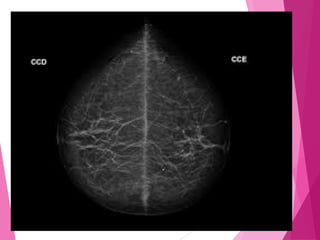

INCIDÊNCIAS DE ROTINA

São realizadas quatro incidências de

rotina:

 Crânio-caudal direita;

 Crânio-caudal esquerda;

 Médio lateral obliqua direita;

 Médio lateral obliqua esquerda.

CRÂNIO CAUDAL

O Paciente deve estar de frente para o

mamógrafo, com a cabeça virada para o

lado oposto ao exame; tubo vertical,

feixe perpendicular à mama.

Centralizar a mama com o mamilo

paralelo ao filme; a parte inferior sobre o

bucky.

Tracionar a mama o máximo possível

antes de aplicar a compressão.